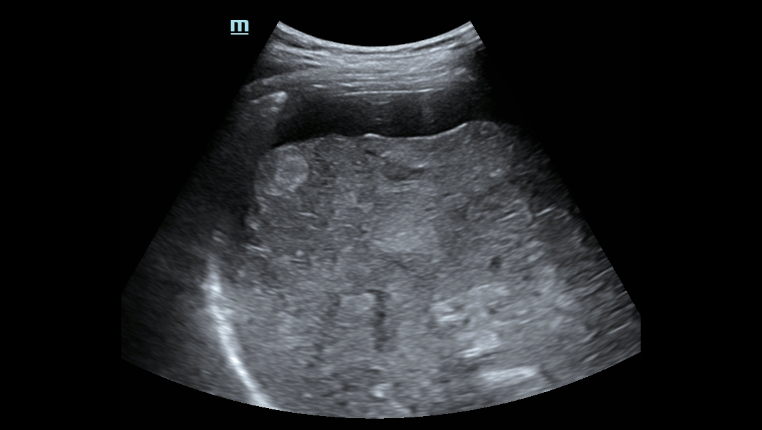

O Hepatus ÃĐ um equipamento de diagnÃģstico profissional n?o invasivo para doen?as hepÃĄticas que fornece resultados quantitativos que indicam o estÃĄgio da fibrose hepÃĄtica. Ele ÃĐ preciso, eficiente, confiÃĄvel e adequado ao acompanhamento de doen?as, abrindo uma nova era para o diagnÃģstico n?o invasivo de doen?as hepÃĄticas.

Ampla gama de aplica??es clÃnicas

? aplicÃĄvel à triagem, ao diagnÃģstico, ao monitoramento e à avalia??o do tratamento da fibrose e da esteatose hepÃĄticas devido a vÃĄrios motivos. Especialmente durante o estÃĄgio inicial.

VÃĄrias solu??es de ultrassom*

â Sonda de ultrassom profissional para facilitar o exame de ascite, etc.

â A excelente qualidade de imagem e as fun??es de ultrassom permitem uma avalia??o abrangente da morfologia e hemodin?mica do fÃgado.

â A excelente qualidade de imagem e as fun??es de ultrassom permitem uma avalia??o abrangente da morfologia e hemodin?mica do fÃgado.